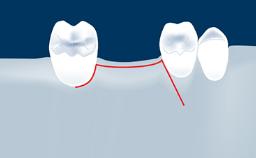

Following tooth loss, alveolar resorption and ongoing pneumatization of the maxillary sinus may lead to vertical and horizontal bone deficits in the posterior maxilla.

This deficit reduces the distance between the maxillary sinus floor and the alveolar process, so that reconstructing the vertical bone height by means of a sinus floor elevation procedure may be a prerequisite for placement of dental implants of the correct dimensions and in the ideal three-dimensional positions in order to achieve optimal functional and esthetic treatment outcomes while respecting relevant anatomical structures.